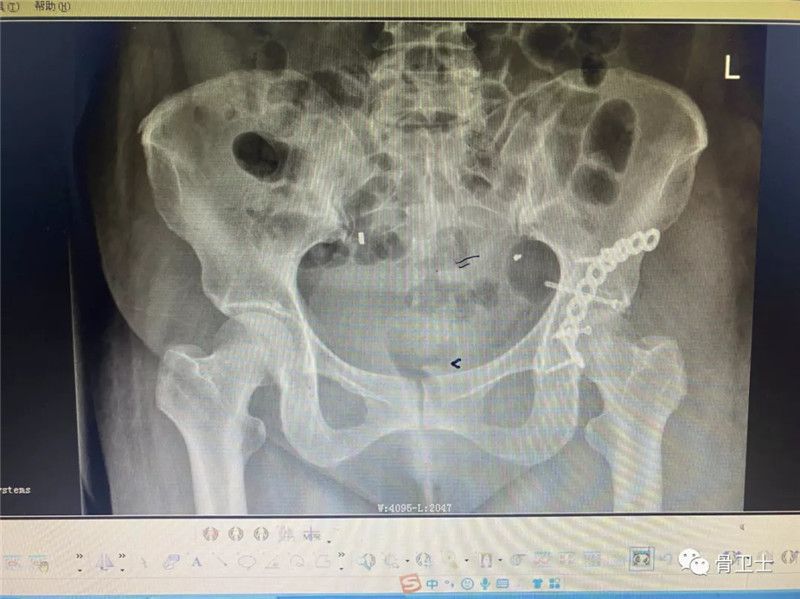

治疗方法:2月22日入院后急诊在静脉全麻下行左股骨头手法复位+左胫骨结节骨牵引术,病情平稳后,于2月25日在全麻下行髋臼骨折切开复位内固定术。

术后影像: